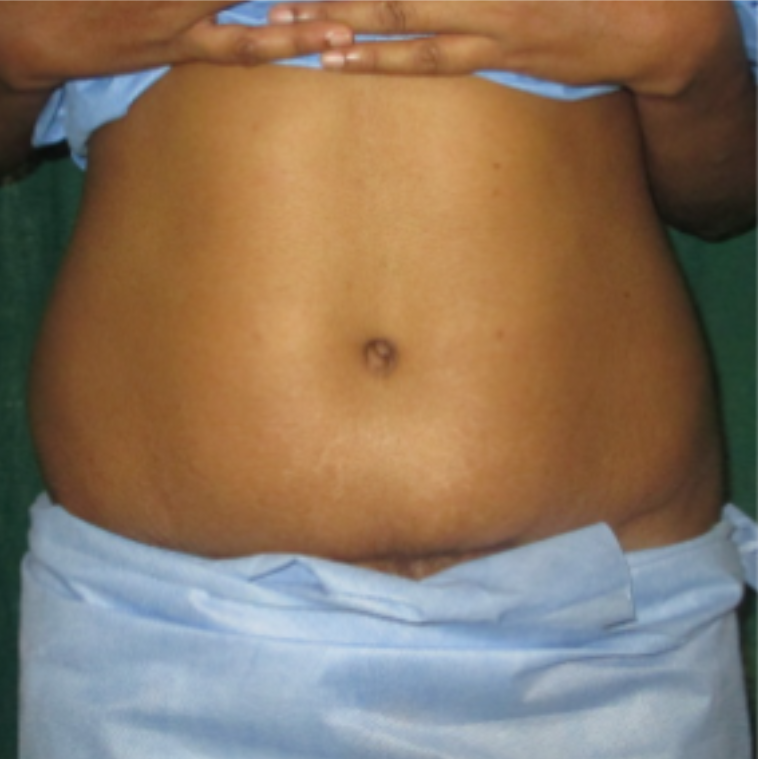

ABDOMINOPLASTY